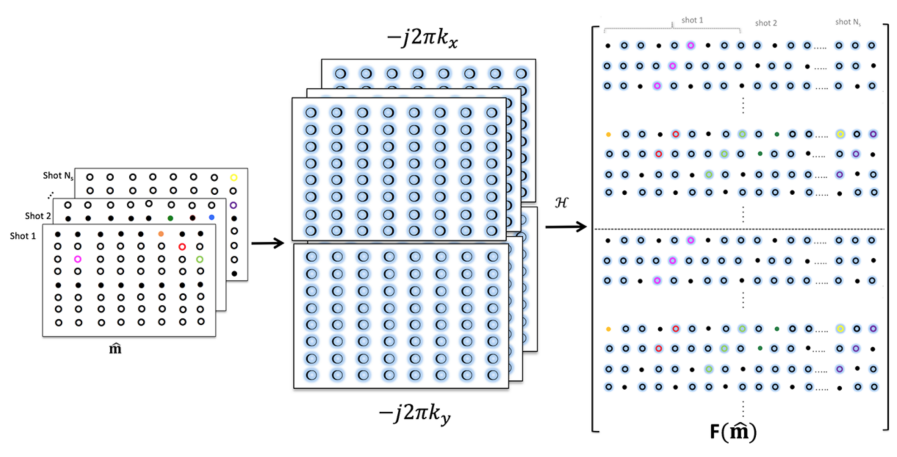

See figure 3 for an illustration of the new lifted matrix , which is highly low-rank. We propose to recover the motion-compensated multishot data using the consolidated nuclear-norm minimization problem that incorporates smoothness regularization (SR):

Fig 3: Illustration of joint matrix lifting for multi-shot data: The Fourier coefficients of the partial derivatives along the x-dimension and y-dimensions are obtained by multiplication using and , respectively. The block Hankel matrices of the each partial derivative are generated and and stacked as shown.